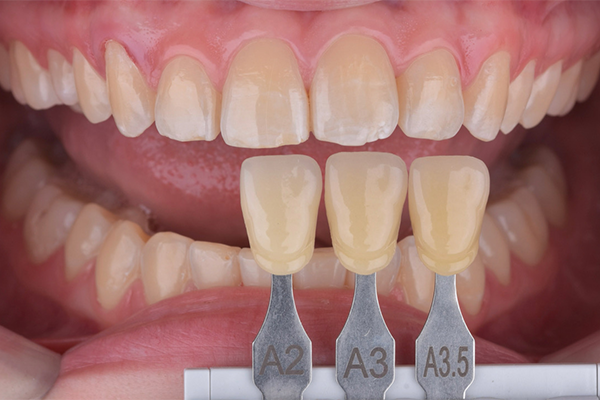

Na primeira consulta, foi realizada a profilaxia dos arcos dentários, com o objetivo de remover biofilme e facilitar a avaliação da coloração dental. Na consulta subsequente, foi realizada a mensuração da cor inicial dos dentes utilizando a escala de cor A-D. Foram identificadas as tonalidades A2 para os incisivos centrais superiores e A3 para os caninos superiores.

3 e 4 | Aspecto inicial, seleção de cor.